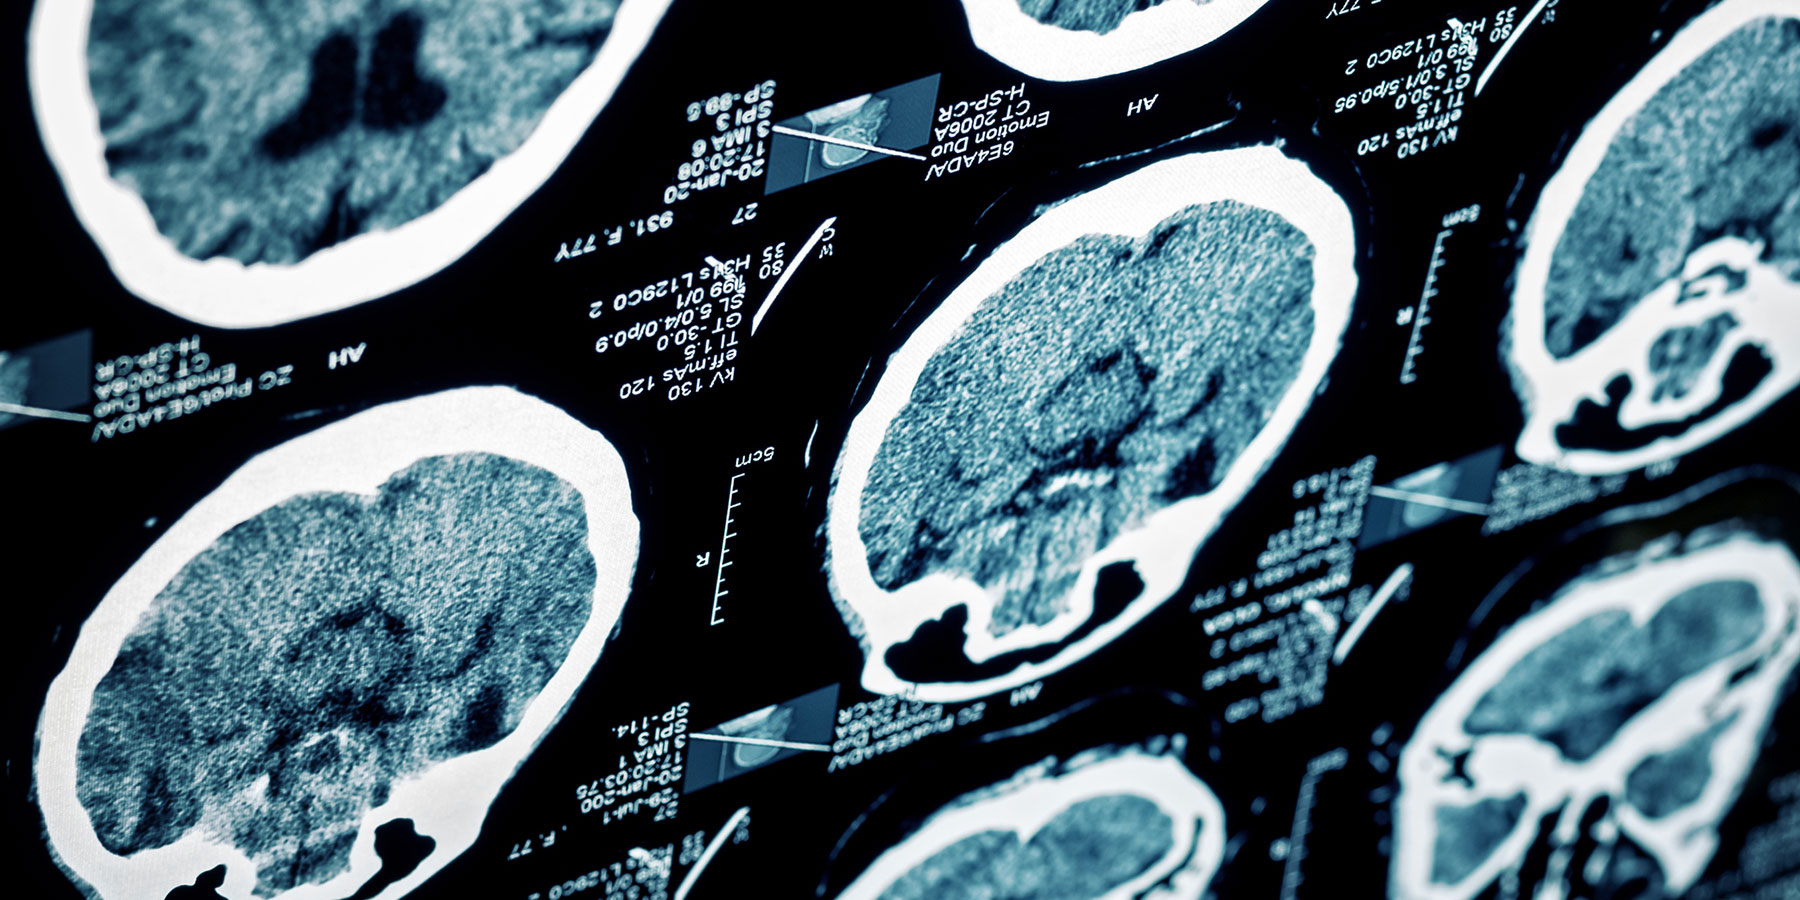

In Alzheimer's disease, clumps of amyloid form plaques around the neurons of the brain, while another protein, tau, accumulates inside the nerve cells in what are referred to as tangles. Plaque and tangles appear first in one region of the brain and then spread, causing gradually deteriorating functional impairment.

In the current study, the researchers studied the extent and distribution of tau and amyloid in the brain tissue of people with Down's syndrome with or without an Alzheimer's diagnosis, and of people who had died with Alzheimer's disease but without any other functional disability.

Their analyses showed that the incidence of tau in the brain tissue of people with Down's syndrome and Alzheimer's disease was higher than in people with Alzheimer's but without Down's syndrome, suggesting that tau is an early change in Down's syndrome.

"Apart from a high level of tau, we also measured a different regional distribution of tau in the brains of people with Down's syndrome and Alzheimer's disease compared to the control group," says the paper's first author Laetitia Lemoine, assistant professor at the Department of Neurobiology, Care Sciences and Society, Karolinska Institutet.